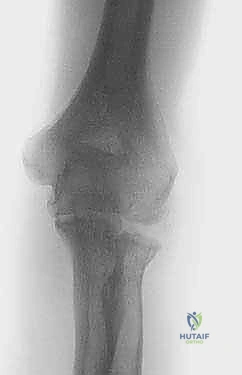

Radiographs show osteophyte formation on the coronoid and olecranon but relatively preserved joint space at the early stages. More advanced stages may be associated with significant joint space narrowing.

Clinical & Radiographic Imaging